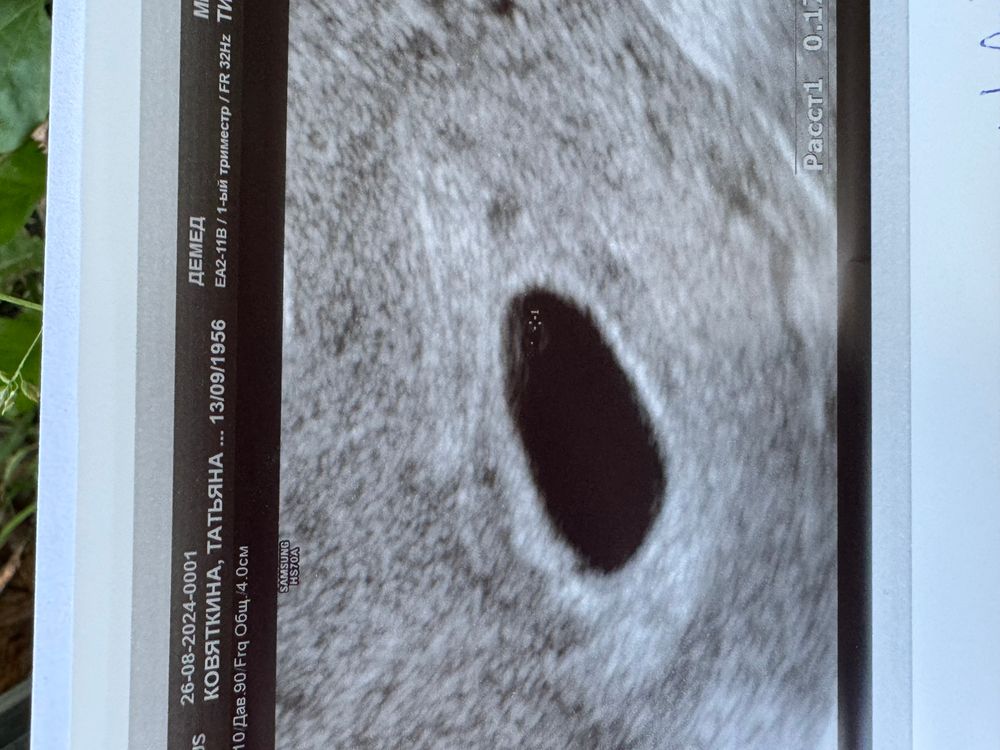

26дпп узи это конец?😭

Я бы дней 5-6 подождала и еще раз сходила на хороший аппарат, у вас пя небольшое, еще есть шанс, что эмбрион появится.

Ирина, раз пя небольшое, значит вообще отстает?( 6 недель по месячным сейчас

Вероника, ну нет, у меня на 32 дпп в 7 недель ровно 17 пя, 7 эмбрион, сб+, в 8 недель пя 29, ктр 18, не расстраивайтесь раньше времени

Я бы сгоняла ра экспертное узи к хорошему узисту, но если результаты такие же то да, тут уже ничего не будет. На 26 дпп уже должен быть эмбрион с сердцебиением.

Скорее всего да... По идее уже должен быть эмбриональный полюс помимо желточного мешочка. Мне очень жаль... Дважды столкнулась с этим, прекрасно понимаю, насколько это неприятно и тяжело переживается. Не сдавайтесь! Идите к заветной цели!

Я думаю надо еще подождать 🙏 если есть ЖП со дня на день должен появится эмбрион дай бог 🙏 переделайте узи хотябы через дня 4

Алёна, жм и на 21дпп был 😭 вот я подождала 5 дней, не видно 😖